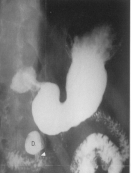

Aspect un ulcere jeune du

duodenum en TOGD mono contrast baryte avec

compression dosee . Image une niche ovalaire

remplisage par baryte avec etat oedemateuse de la

muqueuse peri lesionaire |